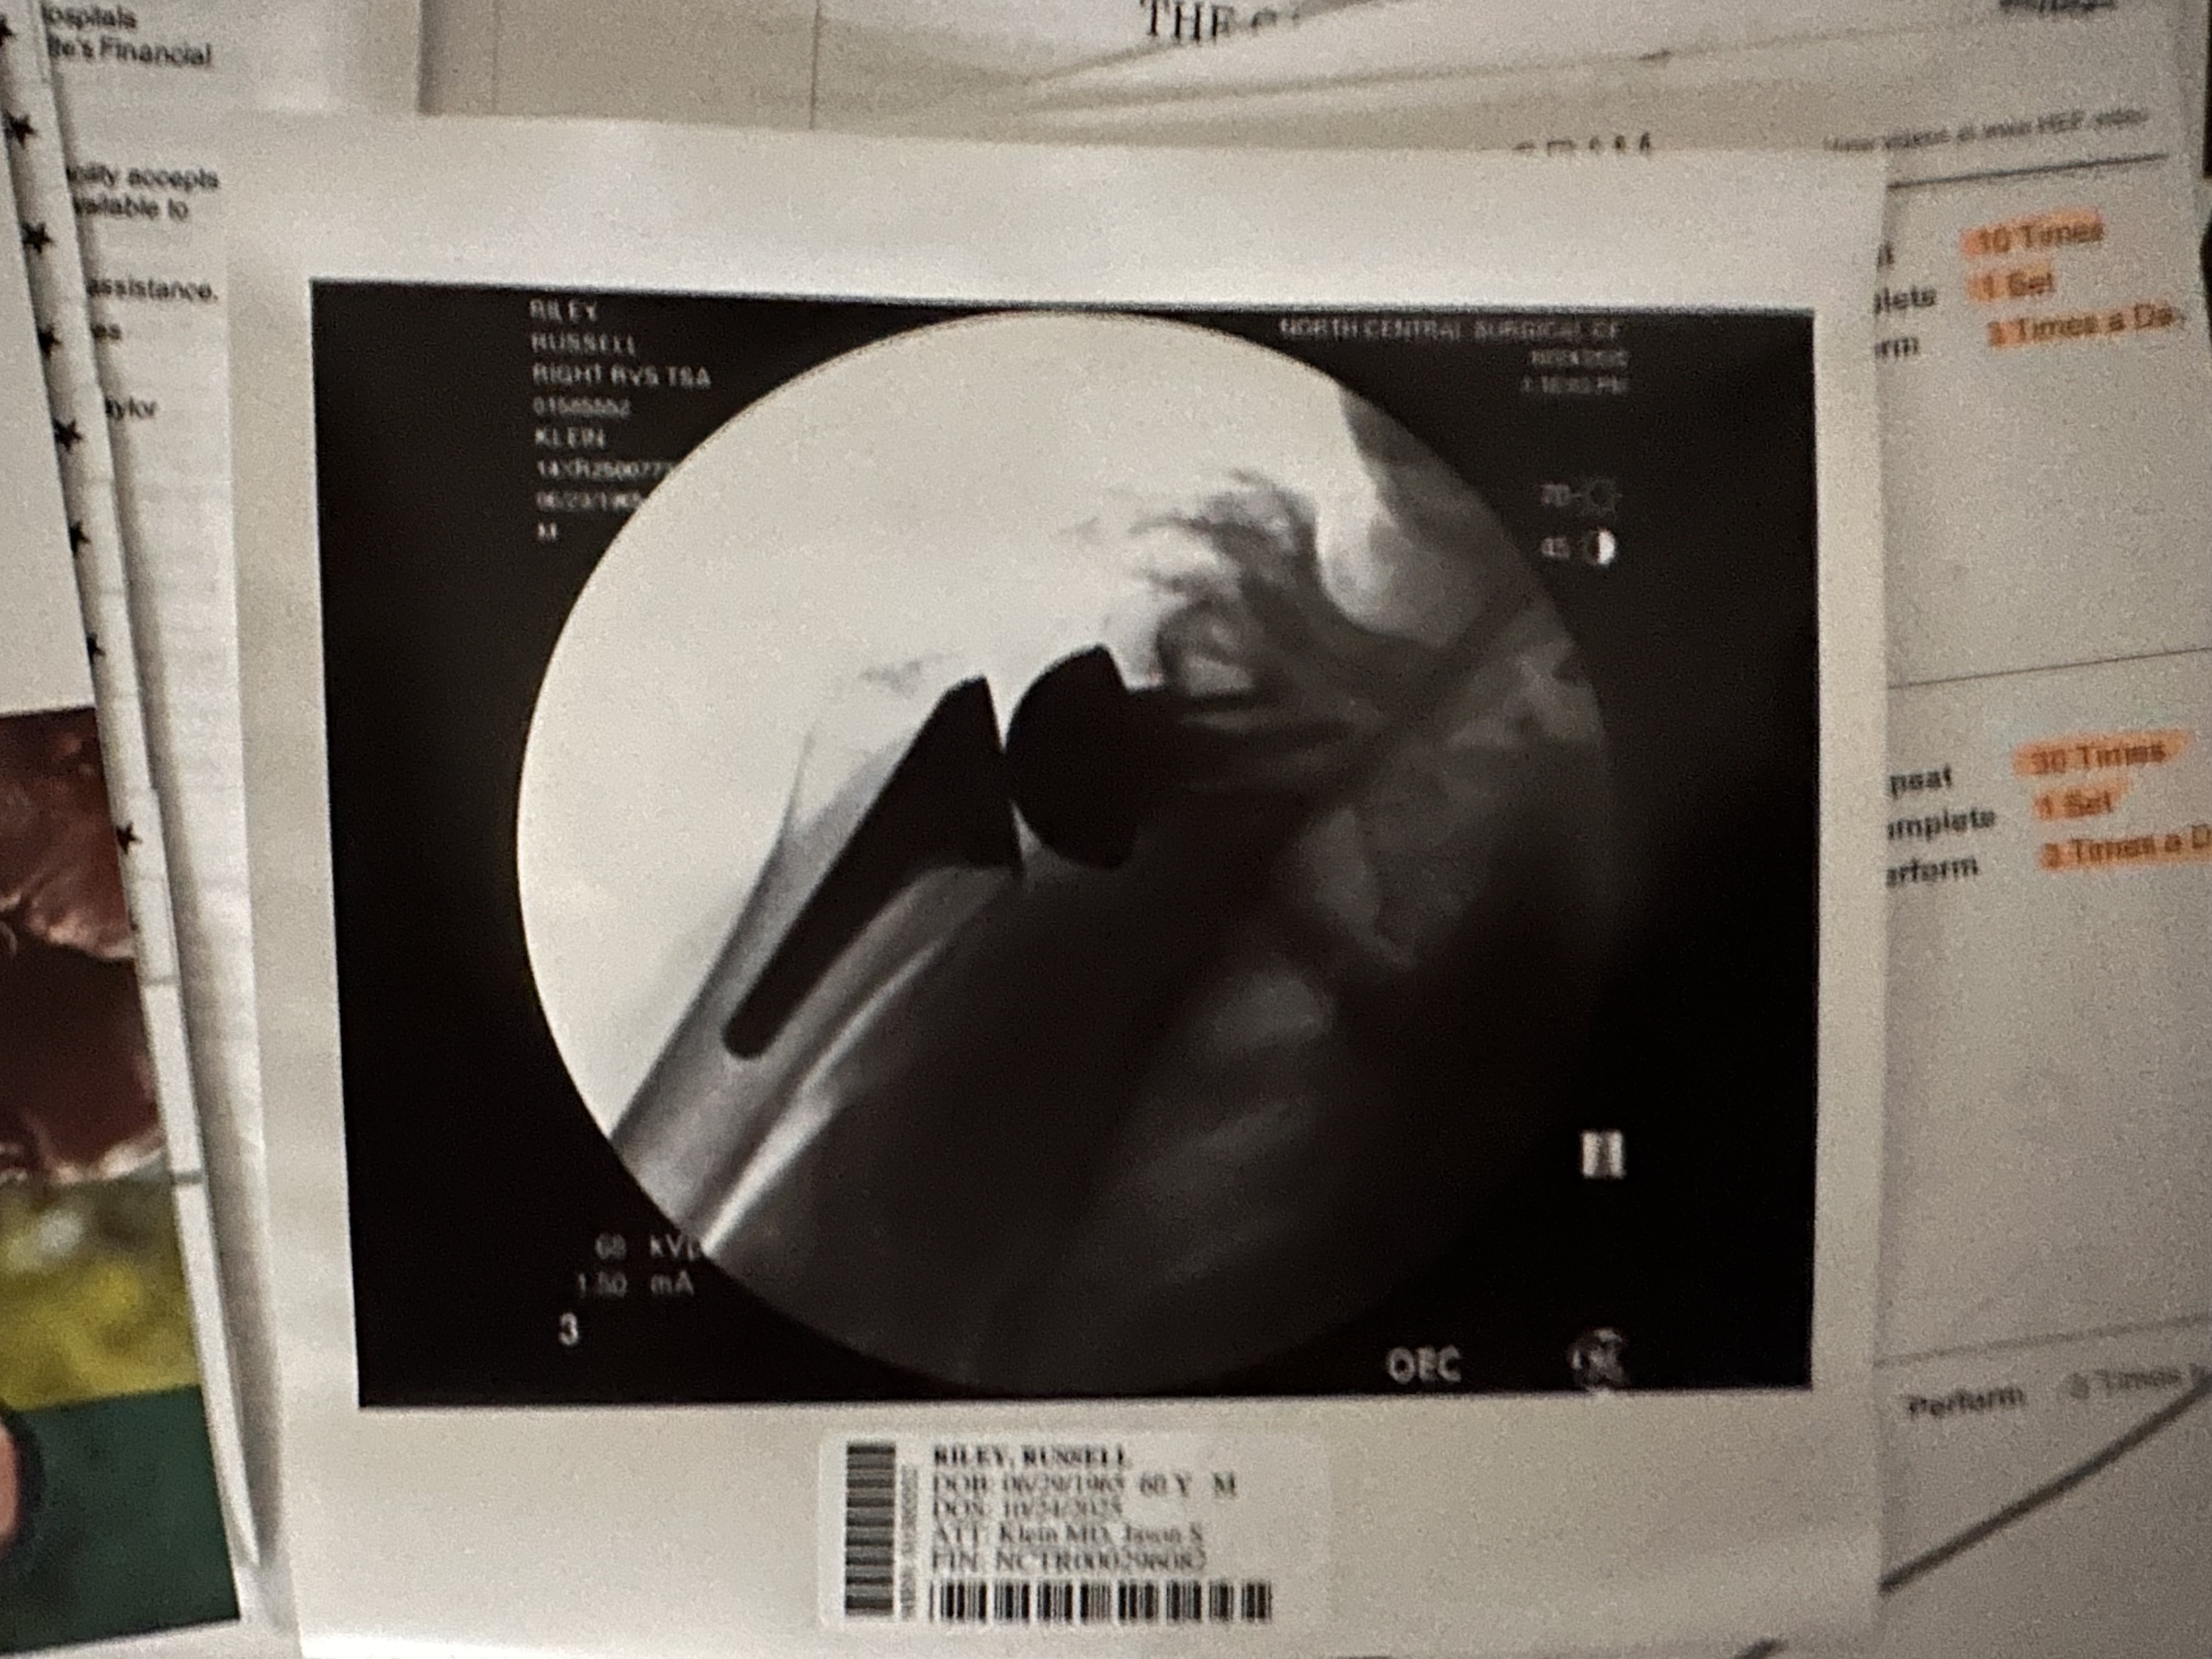

Now for the big show. I will not be able to remember or name names so please know that all of the nurses from the one who put my IV in, and worked on me before the surgery including my anesthesiologist, did a terrific job and made that process for me seamless!! I never worried once. The surgery was a big success and after less than 2 weeks in, I feel great I can move my arm above my head with hardly any pain. I can do my therapy exercises at home with ease. I was in surgery a little longer than normal. Dr. Klein said it was a little worse than he thought once he was inside. I swear he put some bionic stuff in there🤣 because I really feel good only 10 days after surgery.